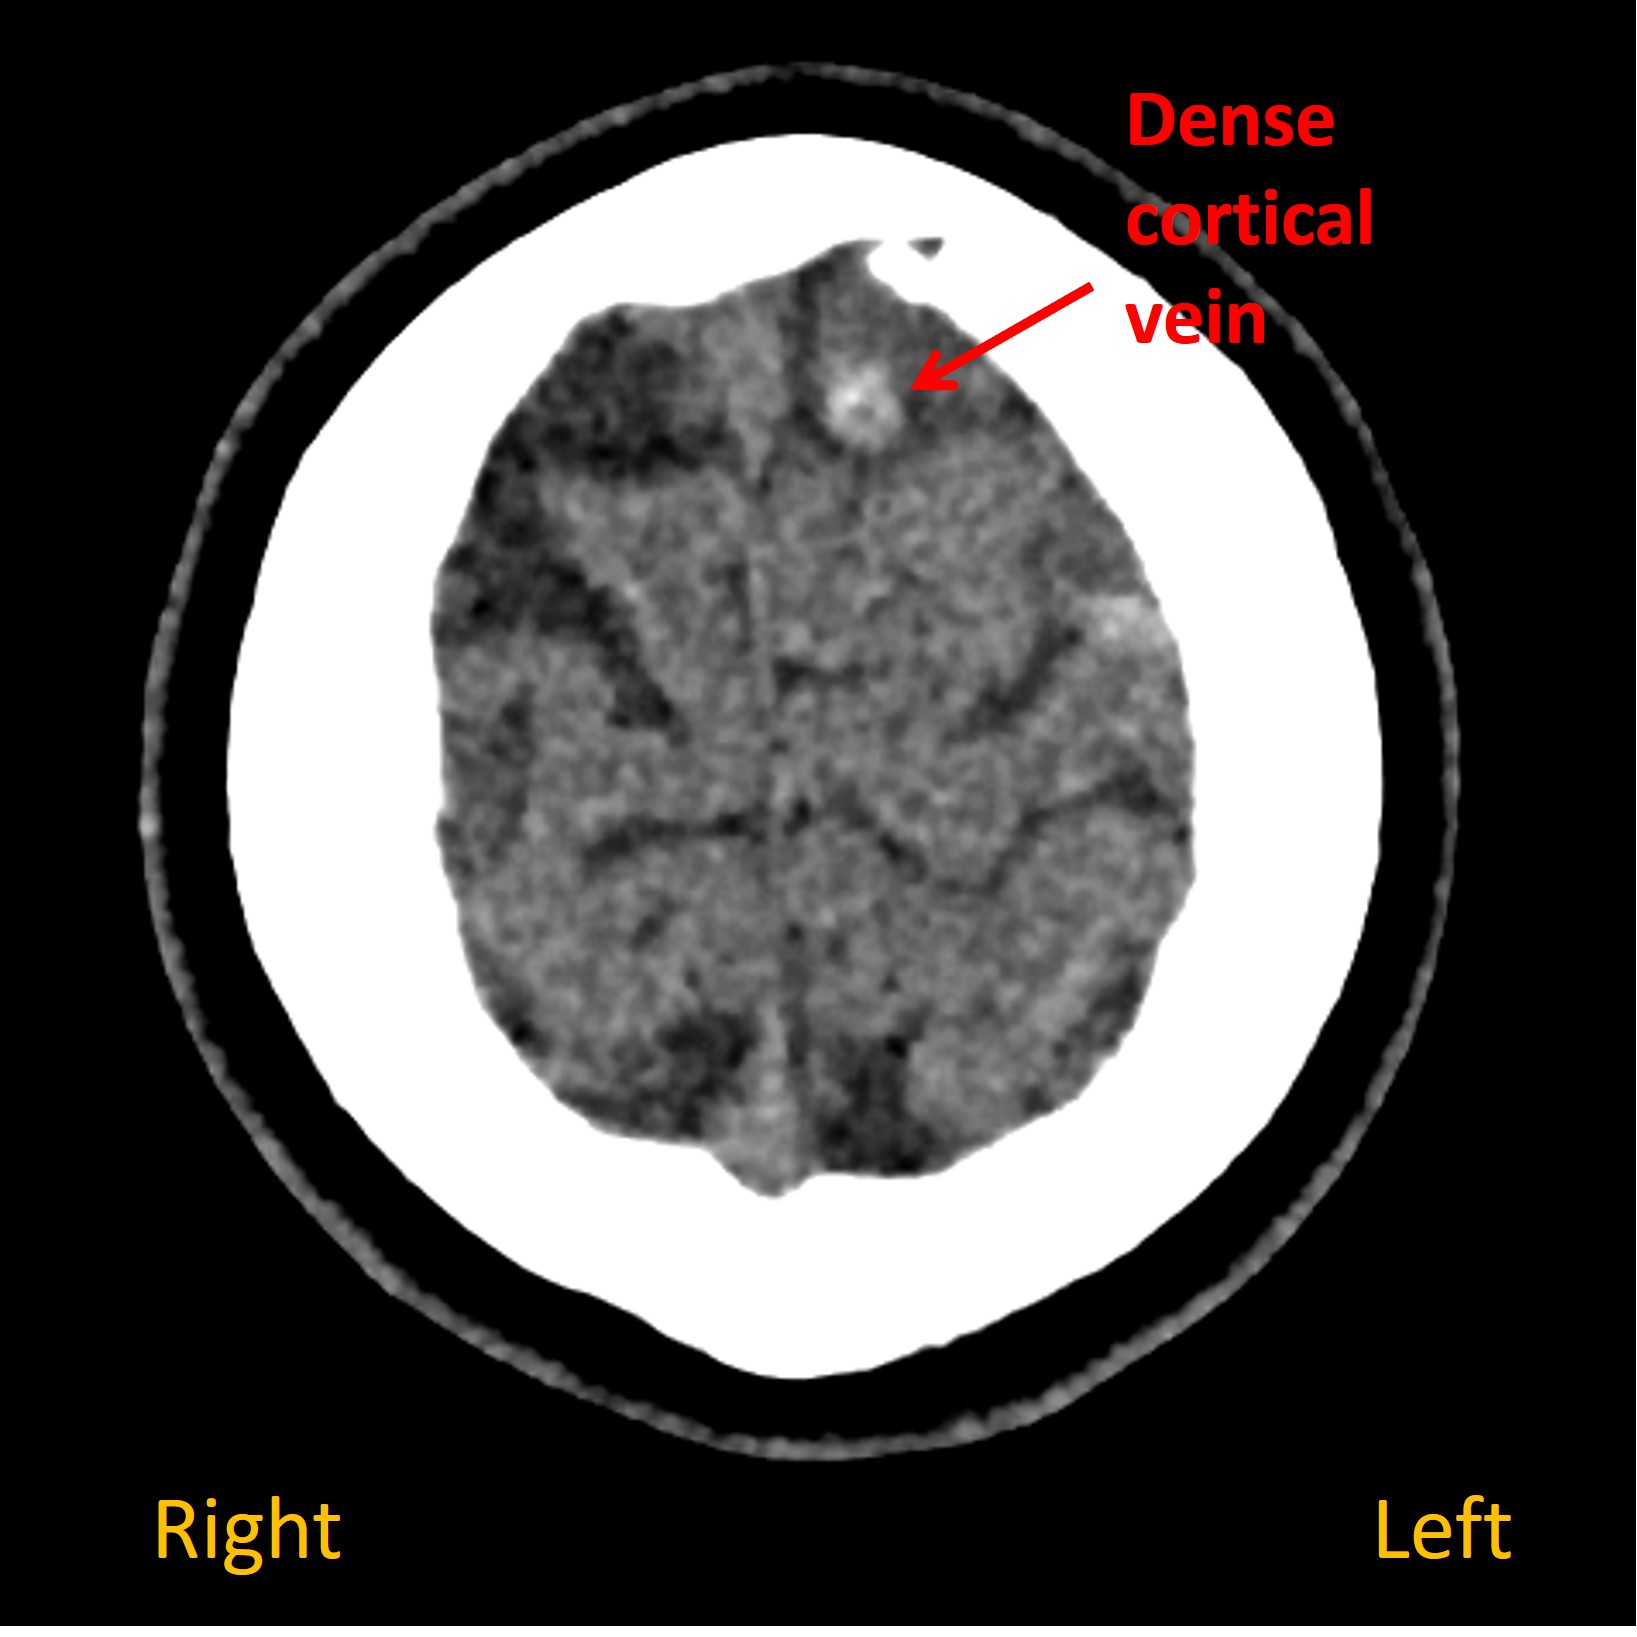

On a plain CT head a dense cortical vein was visible overlying the left frontal lobe, suggestive of static blood ( Images A and B ). A dark area of hypoattenuation was visible in the underlying brain, suggesting a venous infarction (C). Contrast venography identified a filling defect in the vein - confirming cortical venous thrombosis ( D ).